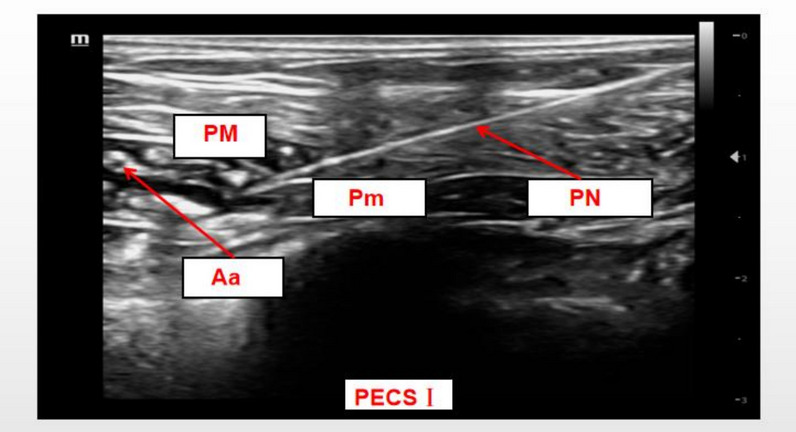

Background: Injury to the sternocostal joint during minimally invasive cardiac surgery frequently results in severe pain, yet there is no established standard for perioperative analgesia. This randomized controlled trial evaluated whether adding 1 μg/kg dexmedetomidine to 0.375% ropivacaine for chest wall fascial plane blocks enhances opioid sparing in ultra-fast-track (UFT) minimally invasive heart valve surgery.

Methods: Seventy-six elective patients were randomized (1:1) in a double-blind manner. The control group received 60 mL of 0.375% ropivacaine, while the DEX group was administered 60 mL of 1 μg/kg dexmedetomidine plus 0.375% ropivacaine. The primary outcomes were intraoperative remifentanil use and 24-h postoperative sufentanil consumption, which served as co-primary endpoints to evaluate opioid-sparing effects. Secondary outcomes included 24-h postoperative sufentanil consumption, 24-h oxycodone use, patient-controlled analgesia (PCA) activations, episodes of Visual Analog Scale (VAS) scores ≥ 3 within 48 h, time to recovery of consciousness, time to extubation, duration of intensive care unit (ICU), and hospital stays, and complications.